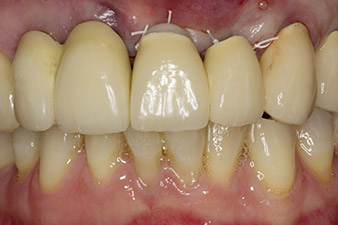

In order to compensate for the periodontal bone loss and achieve an aesthetically pleasing result, the implantation was combined with guided bone regeneration (GBR) with xenogenic replacement material and a collagen membrane

(Fig. 5 and 6).

In this case study, the situation was resolved with an implant at position 22 in the first procedure and an additional one at the position of the extracted tooth 23 later in the course of the treatment. The second implant was inserted following successful osseointegration of implant 22. The revised bridge was reinserted until implant 23 healed in place and the shaping for the permanent restoration was complete. The advantages of this gradual approach include the implants’ being able to accept loads more resiliently and mature hard and soft tissues (5).